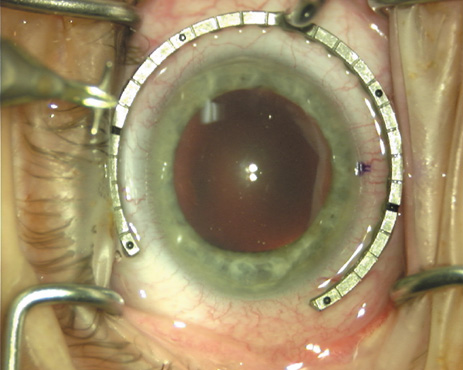

The extent of arc to be incised may be demarcated in several different ways. Our preferred method makes use of a modified Fine-Thornton fixation ring (Nichamin Fixation Ring and Gauge; Mastel Precision, Storz, Rhein Medical). This instrument serves to fixate and position the globe in order to optimize incision placement, as well as to delineate the extent of arc to be incised. One visually extrapolates from the limbus to marks on the surface of the ring. Each incremental mark is 10 degrees apart, and bold hash marks (180 degrees) opposite to each other serve to align and center the incision over the steep meridian. This approach obviates the need to ink and physically mark the cornea. If one desires, particularly when first gaining experience with LRIs, a two-cut RK marker may be used to place ink marks upon the cornea to show the exact extent of arc that is to be incised, in conjunction with the fixation ring/gauge (Fig. 4). Alternatively, various press-on markers are available, such as those made by Rhein Medical (Dell-Nichamin Marker, Nichamin-Kershner Marker, or the Ruminson Marker) (Fig. 5). ASICO and other instrument companies offer a full line of dedicated markers, rings, and blades for performing LRIs.

Fig. 4. The Nichamin Fixation Ring and Gauge serves to both fixate the globe and delineate the extent of arc to be incised; a two-cut radial marker may be used to mark the extent of arc to be incised, and the Mastel Nichamin Force AK Diamond Blade with preset depth of 600 microns.

Fig. 9. The broad hash marks of the fixation ring/gauge are centered over the 75-degree meridian, using the 6:00 limbal mark for orientation. Alternatively, a Mendez gauge may be used. (Reprinted from Hardten DR, Lindstrom RL, Davis EA. Phakic Intraocular Lenses: Principles and Practice. Thorofare, NJ: SLACK Incorporated, 2004, with permission.)